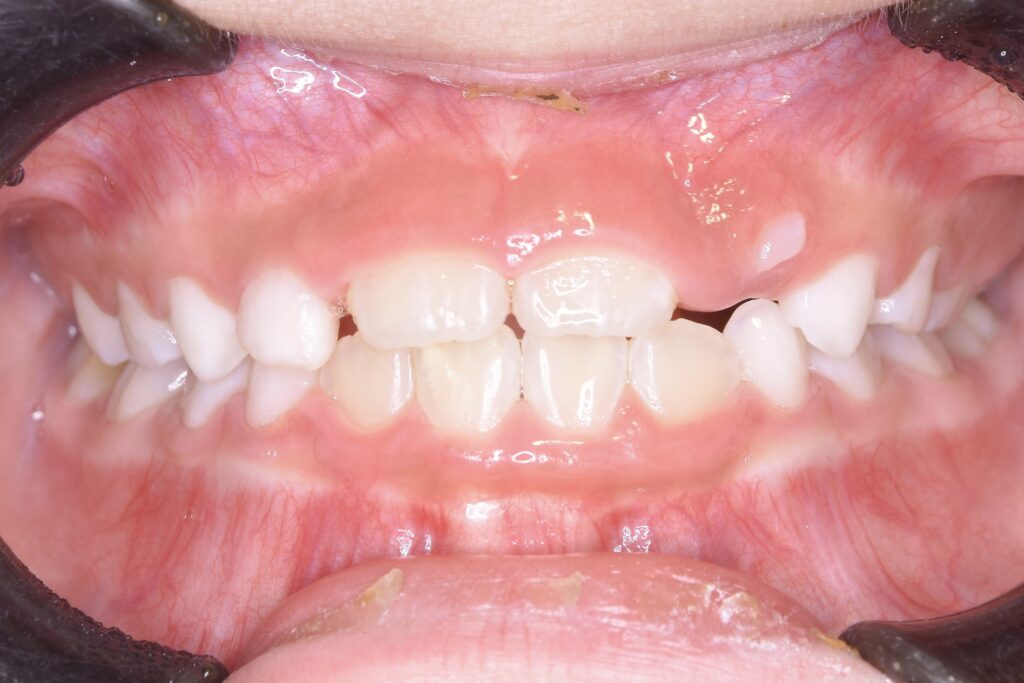

BEFORE

主訴

右下の歯が飛び出ているので治したい。

診断名・主な症状

過蓋咬合

年齢

5歳

治療内容

上下の歯並びの幅を拡げつつ、前歯の関係を改善しました。

使用装置

急速拡大装置

リンガルアーチ

機能的矯正装置(マイオブレース)

抜歯部位

抜歯なし

治療期間

2年 + 後戻り止め期間(5年)

通院回数

25回

費用

50万円程度(税別)

リスク・副作用

痛み、歯肉退縮、歯根吸収、抜歯に伴う出血や腫れが生じることがあります。